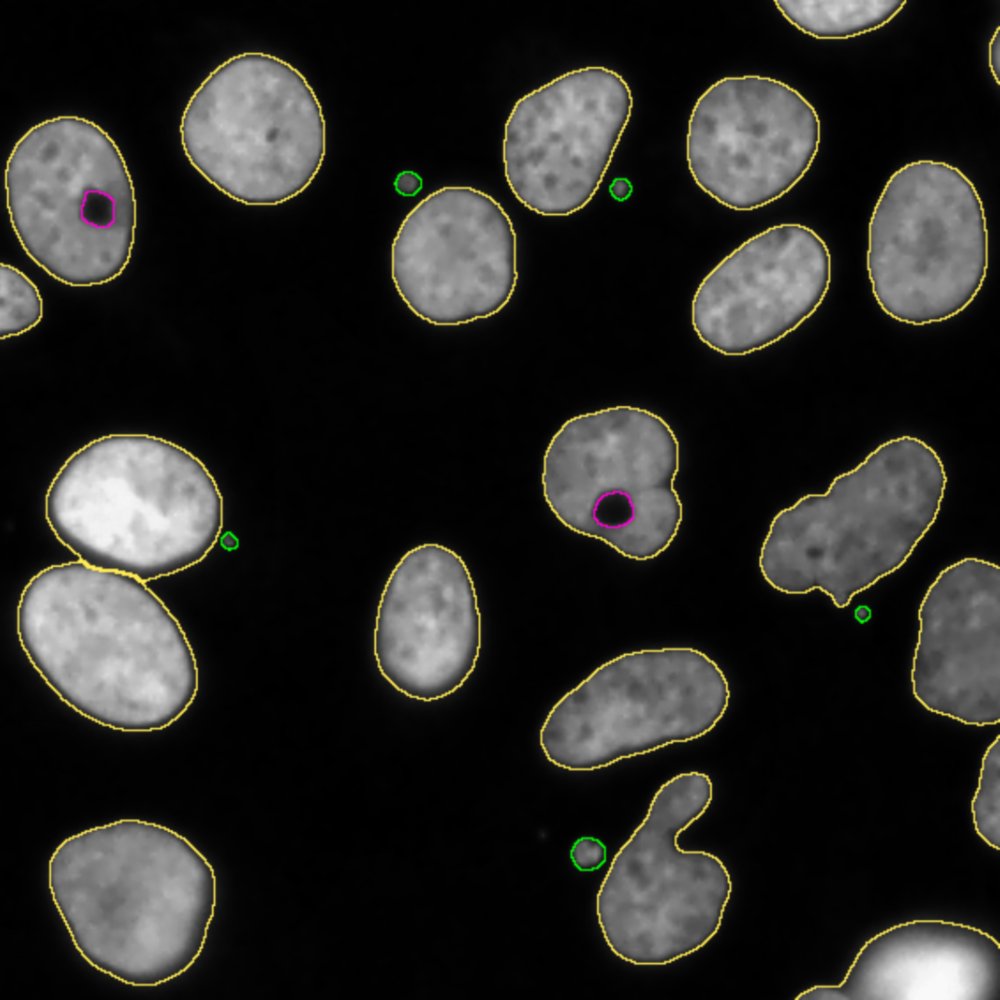

Un equipo de la Universidad de Barcelona y del IRB Barcelona ha diseñado una nueva herramienta bioinformática para facilitar la identificación de las alteraciones cromosómicas que son características de las células tumorales. Este nuevo sistema de detección, conocido como QATS (QuAntification of Toroidal nuclei in biological imageS), es una herramienta computacional de procesamiento de imágenes biológicas que contribuirá a mejorar la investigación y la clasificación de los tumores gracias a su capacidad para identificar y cuantificar automáticamente fenotipos asociados a la inestabilidad de los cromosomas en el núcleo de las células tumorales.

Las células tumorales son capaces de sobrevivir con altos niveles de inestabilidad cromosómica. La nueva herramienta QATS es un sistema predictor que ayudará a identificar y cuantificar automáticamente los núcleos toroidales —unos nuevos biomarcadores de la inestabilidad cromosómica— en imágenes biológicas.

«Los núcleos toroidales son fenotípicamente diferentes de los núcleos normales, ya que presentan una forma de anillo y un vacío que contiene material citosólico. En el ámbito de la investigación, han sido caracterizados recientemente como biomarcadores importantes de la inestabilidad cromosómica, y representan una vía innovadora para comprender y combatir el cáncer», detalla la Dra. Caroline Mauvezin, del Departamento de Biomedicina de la UB.

«Tradicionalmente, el nivel de inestabilidad cromosómica en células cancerosas solo se evaluaba mediante la cuantificación de micronúcleos, que son estructuras irregulares derivadas del núcleo celular que pueden contener cromosomas o fragmentos cromosómicos», añade la investigadora.